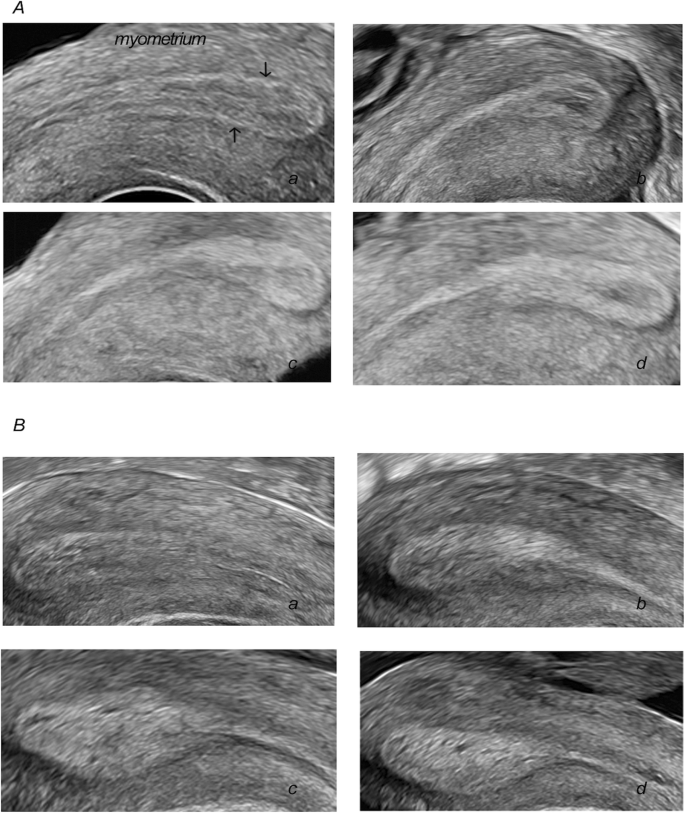

Following publication of the original article [1], the authors reported an error in the order of the figures.

The Fig. 1 published is supposed to be Fig. 5. The Fig. 2 published is supposed to be Fig. 1. The Fig. 3 published is supposed to be Fig. 2. The Fig. 4 published is supposed to be Fig. 3. The Fig. 5 published is supposed to be Fig. 4. The correct order of the figures are as follows: